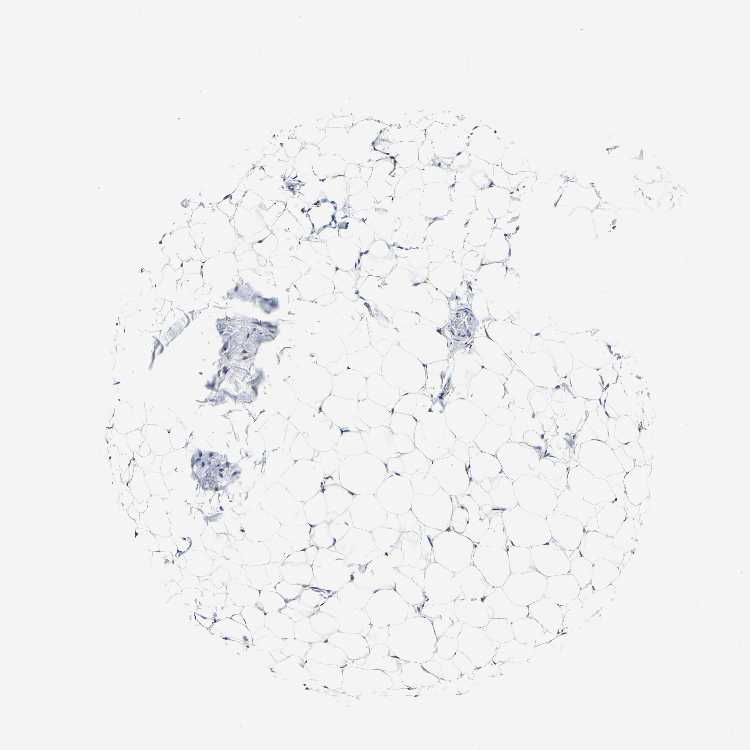

ADIPOSE TISSUE - Antibody stainingi

Antibody staining in the annotated cell types in the current human tissue is reported as not detected, low, medium, or high, based on conventional immunohistochemistry profiling in selected tissues. This score is based on the combination of the staining intensity and fraction of stained cells.

Each image is clickable and will lead to virtual microscopy that enables deeper exploration of all samples and also displays staining intensity scores, fraction scores and subcellular localization as well as patient and tissue information for each sample.

Antibody HPA018884Antibody CAB012463

Adipocytes MediumMedium